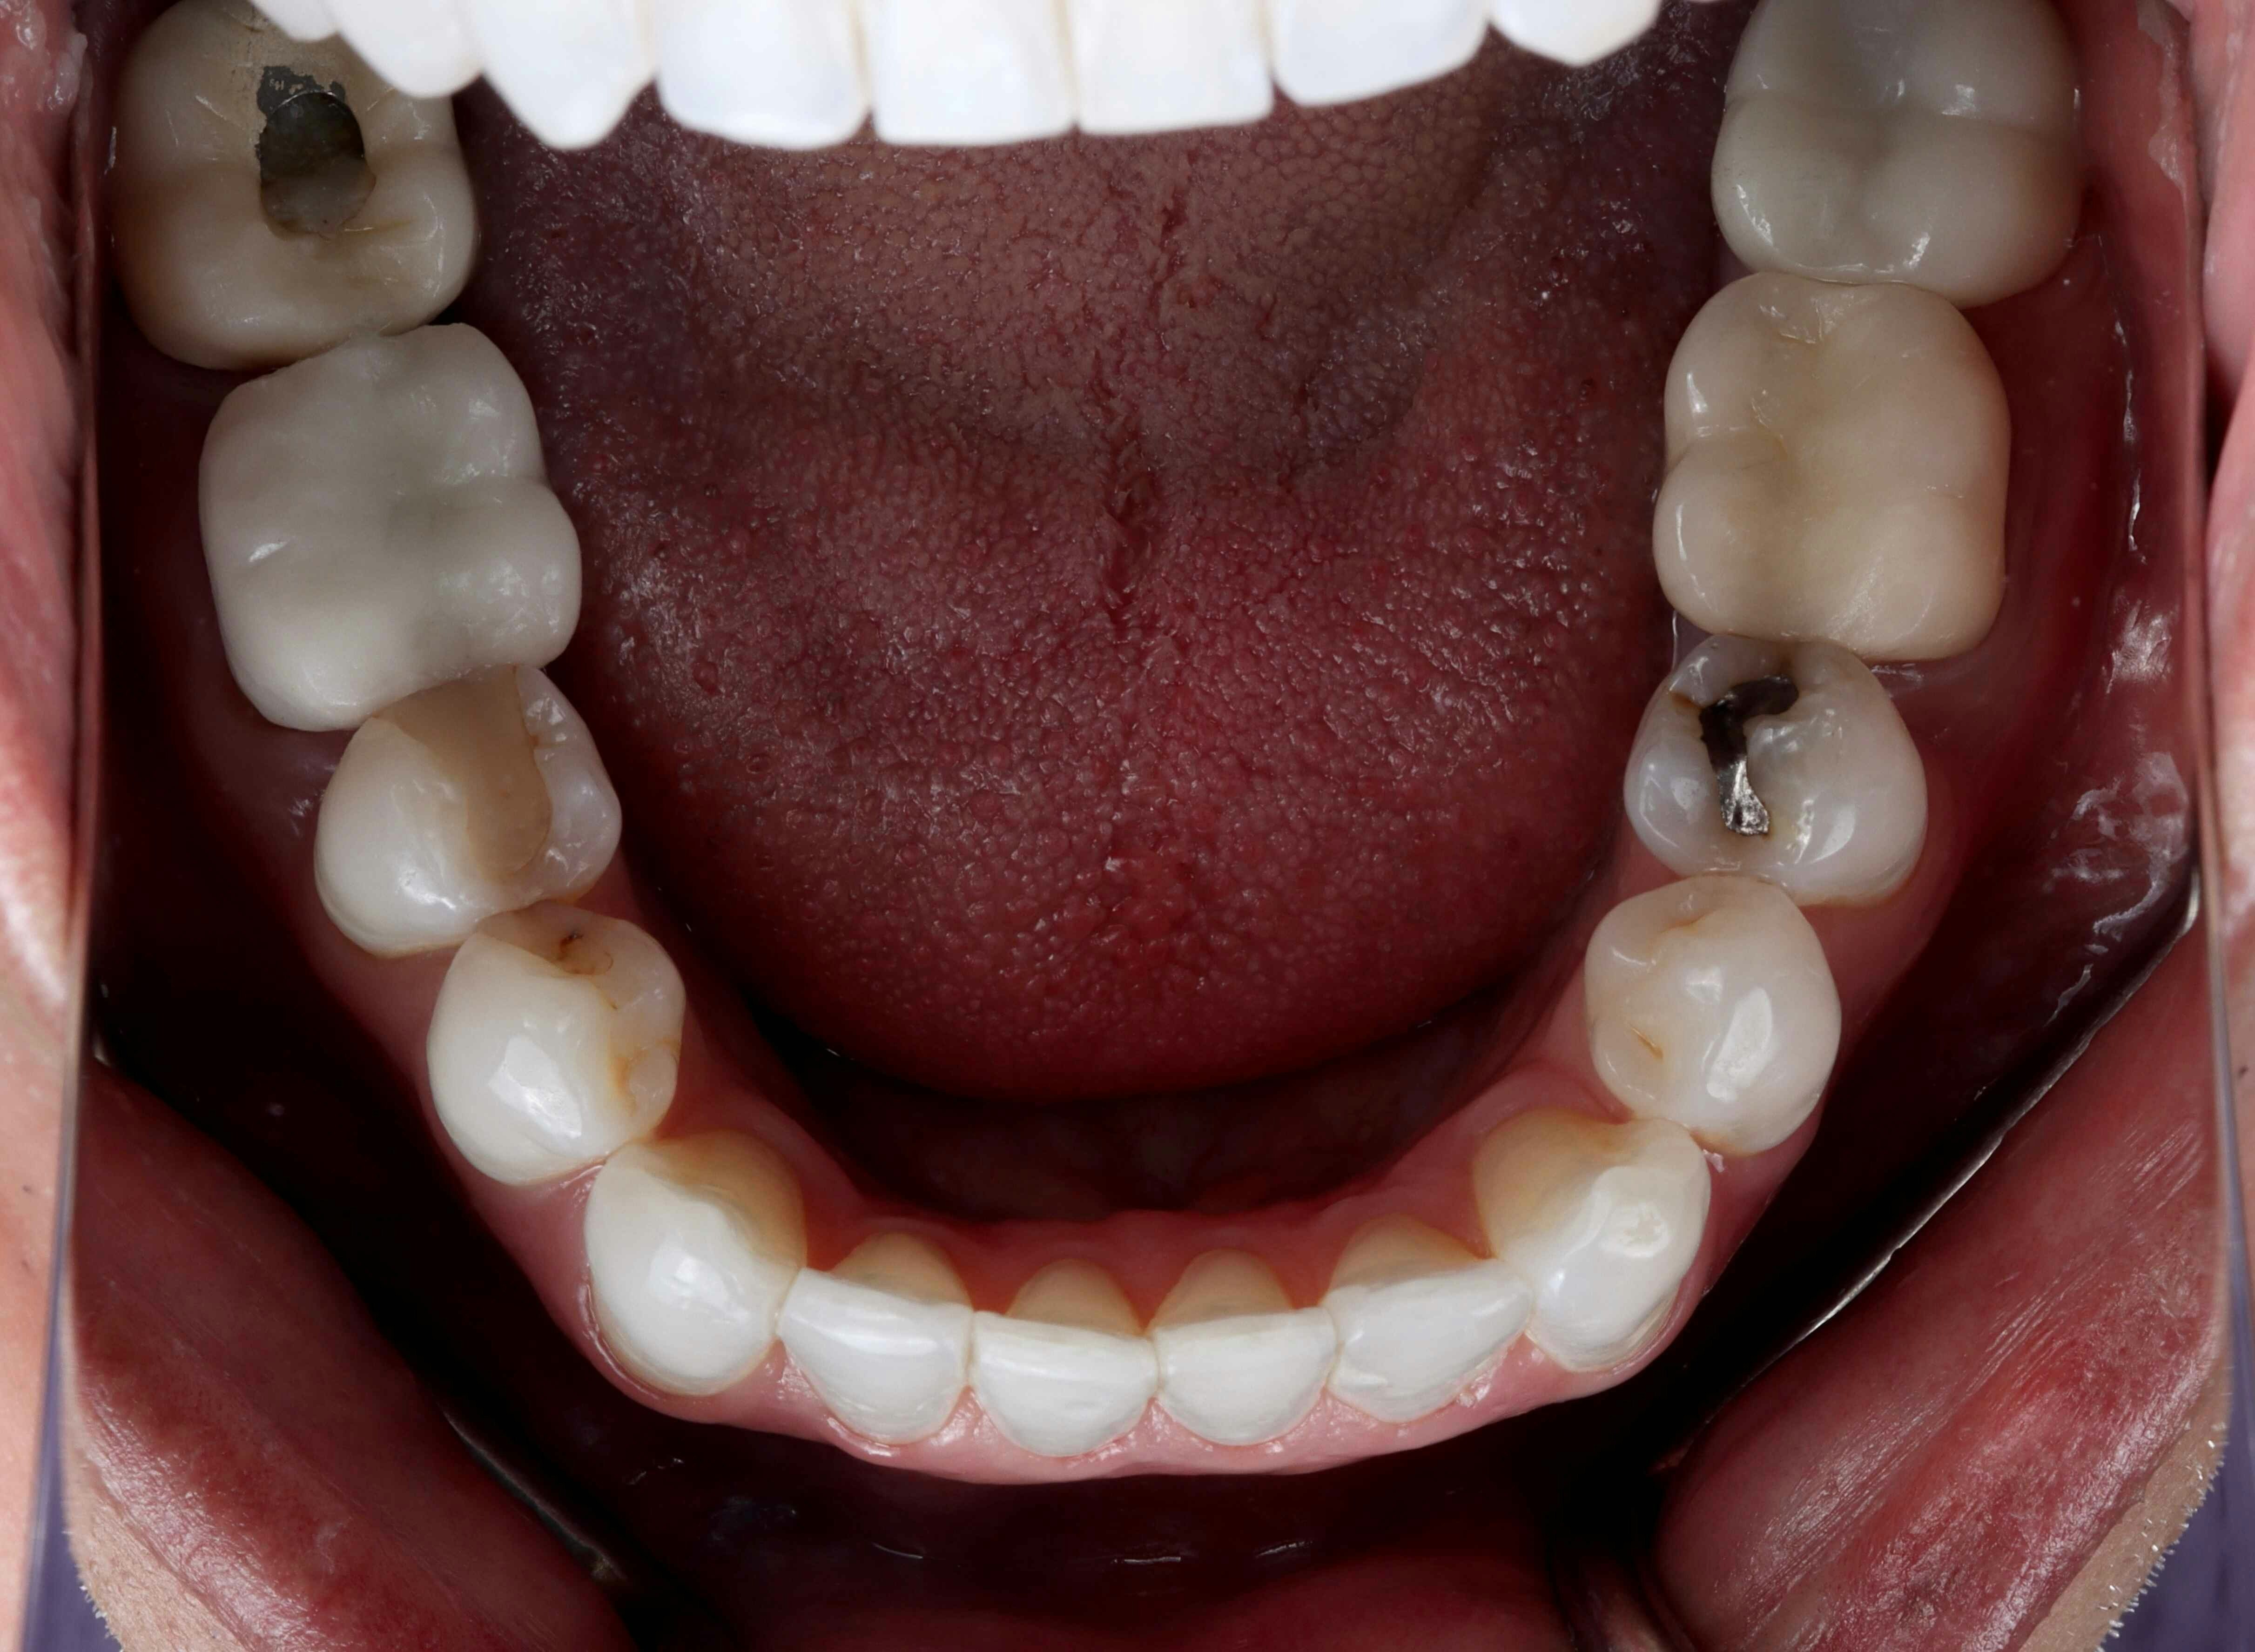

One of the main issues Harsha was dealing with was his habit of clenching and grinding his teeth. On top of that, many of his lower crowns were made flat, without the natural grooves and anatomy that teeth should have. These grooves and valleys are there for a reason, and when they're not properly included in dental work, it can lead to problems down the road.

Once the Invisalign treatment was complete, we replaced Harsha's lower crowns with new ones that had the proper anatomical features. This was a crucial step in ensuring that his bite would function correctly and comfortably.